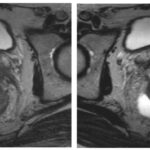

Imágenes de resonancia magnética